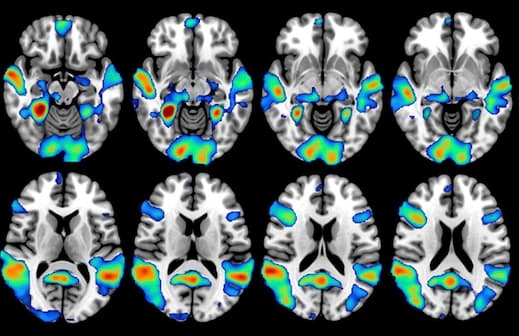

Les résultats ont montré une réponse accrue au bleu de méthylène dans le cortex insulaire bilatéral, une zone profonde du cerveau associée à des réponses émotionnelles, pendant un test qui mesurait le temps de réaction à un stimulus visuel. Les résultats de l’IRMf ont également montré une réponse accrue au cours des tâches de mémoire à court terme impliquant le cortex préfrontal du cerveau, qui contrôle le traitement des souvenirs, le lobe pariétal, principalement associé au traitement de l'information sensorielle, et le cortex occipital, le centre de traitement visuel du cerveau. En outre, le bleu de méthylène a été associé à une augmentation de 7% dans les réponses correctes lors d’un test sur la mémoire.

Les résultats suggèrent qu’une faible dose orale unique de bleu de méthylène peut réguler certains réseaux cérébraux liés à une attention soutenue et à la mémoire à court terme. "Ce travail fournit certainement une base pour les essais futurs à base de bleu de méthylène sur le vieillissement en santé, les troubles cognitifs, la démence et d'autres facteurs qui pourraient bénéficier de l'amélioration de la mémoire induite par les médicaments", conclut le Dr Duong.